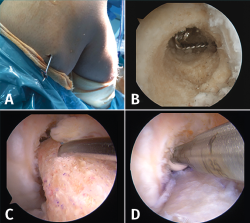

La cirugía de recambio de la plastia en un tiempo se inicia habitualmente con una revisión artroscópica convencional a través de los portales anteromedial y anterolateral. Después de la revisión artroscópica, se realiza la limpieza de los restos de la plastia previa, se retira el material de fijación y, posteriormente, se reconstruye el LCA con la nueva plastia (Figura 6).

Figura 6. Cirugía de revisión del ligamento cruzado anterior (LCA) en un tiempo. A: retirada del material de fijación previo. Casualmente, al utilizar el mismo túnel femoral la aguja guía permitió localizar y extraer el implante de fijación extracortical; B: restos de material en el túnel femoral que deben retirarse previamente a la introducción de la nueva plastia; C-D: el sobredimensionamiento del túnel femoral previo puede compensarse con un taco óseo de mayor diámetro asociado a un tornillo interferencial.

En cuanto al túnel óseo femoral, cuando está localizado en la posición correcta, se suele realizar el nuevo túnel óseo con un diámetro mínimamente superior al previo con el objetivo de retirar los restos de la plastia. La longitud del nuevo túnel dependerá de la plastia que el cirujano haya escogido para la cirugía. En el caso de un injerto con taco óseo, este se ajustará al diámetro del túnel realizado y, posteriormente, se fijará con un tornillo interferencial o bien un sistema de fijación cortical externa en el fémur. Cuando el túnel femoral se encuentre lejos de la localización del nuevo túnel, se puede rellenar el túnel previo con injerto óseo o un tornillo interferencial, con el fin de evitar la fractura de la pared del nuevo túnel. Esto puede suceder cuando se realiza una revisión sobre una técnica de reconstrucción transtibial previa (Figura 7).